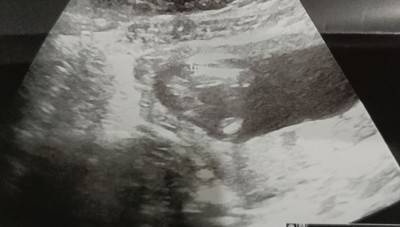

Merhabalar ikili testte erkek dendi 14+6 da baya zorlanarak bakti kiz dendi.detaylidada degisirmi ikisindede bacak arasina bakti erkek derken kordonu yandan geciyodu bacak arasi acikti yani karistirmamistir diye dusunuyorum ancak kafam cok karisti 12 ve en son goruntusunu birakiyorum tahminde bulunurmusunuz

Gebelik haftası 15